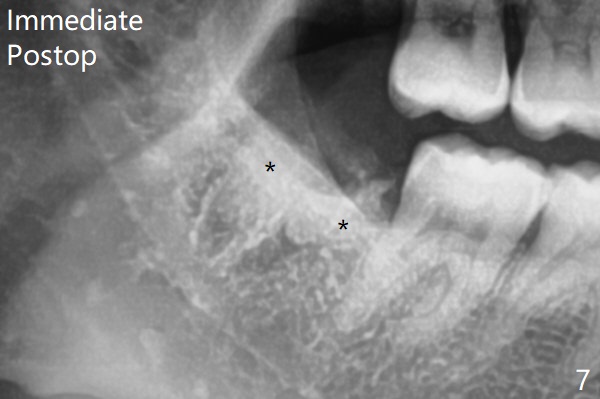

Since no buccal trough is made for extraction, the external oblique ridge (*) is present at #17 and 32 before and after surgery. Bond Apatite is placed with Collagen Plug (Fig.7).